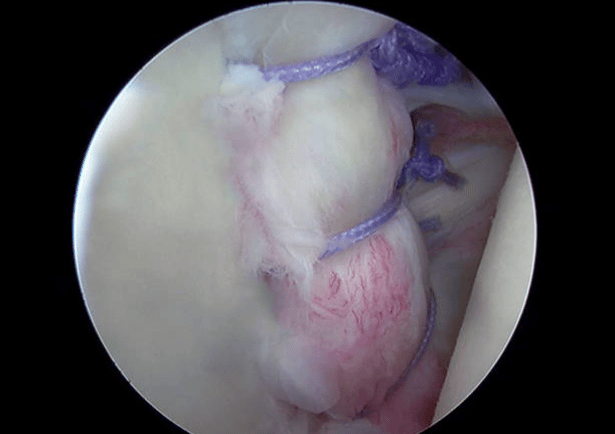

La artroscopia de hombro es un procedimiento quirúrgico mínimamente invasivo que permite diagnosticar y tratar diversas afecciones dentro de esta articulación. A través de pequeñas incisiones, el especialista introduce una cámara diminuta (artroscopio) y herramientas especiales para visualizar y reparar los tejidos dañados sin necesidad de abrir completamente el hombro.

La artroscopia se realiza en quirófano, bajo anestesia regional o general. A través de incisiones milimétricas, se introduce el artroscopio para explorar el interior del hombro y se utilizan instrumentos quirúrgicos especiales para reparar los tejidos según sea necesario. Al tratarse de una técnica mínimamente invasiva, los tiempos de recuperación son menores en comparación con la cirugía abierta.